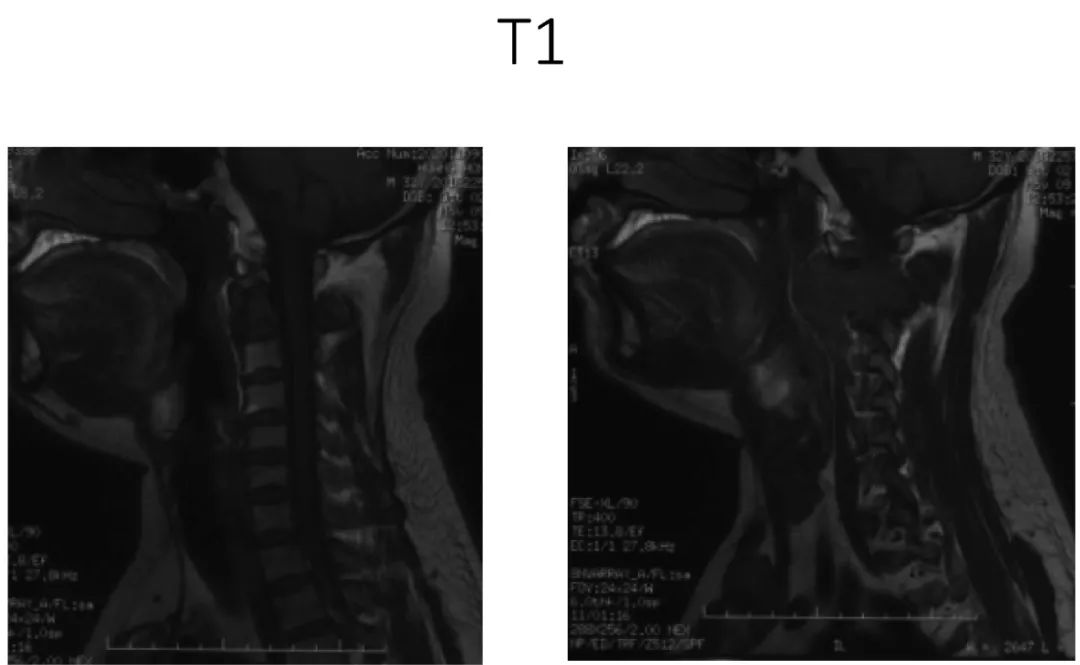

病史:male, 63 y/o

Neck pain for 3 months

影像资料:

诊断:C2椎体肿瘤